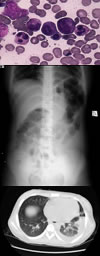

骨髓细胞学检查骨髓增生活跃,红系增生明显减低(图1).

影像学检查全腹立位X线片示腹部散在数个液平面,左上腹肠管胀气扩张(图2).

腹部CT示腹水;右肾盂饱满,双输尿管近端充盈,右侧张力偏高;肠管淤张。肺部高分辨CT示左下肺实质浸润(图3);双侧胸腔积液;腹腔积液。腹部增强CT示腹水;肠系膜上动脉近端管腔形态欠规则,管壁前缘略厚,可见“梳状”血管排列;左下腹局部小肠管腔增粗,下腹部小肠淤张.